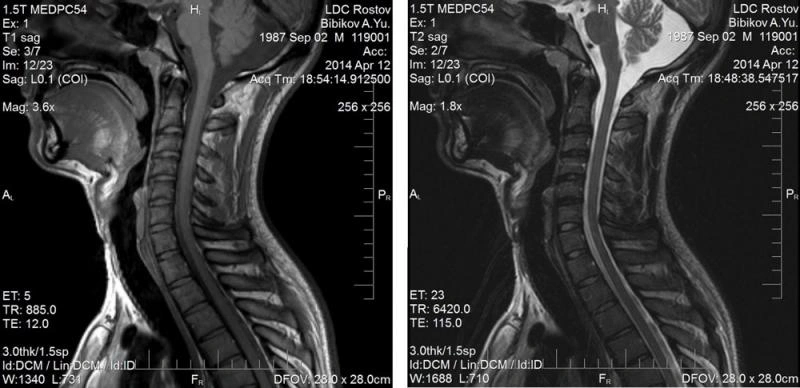

МРТ шейного отдела позвоночника + сосуды

Шейный отдел позвоночника,  является самым верхним отделом позвоночного столба. Он состоит из 7 позвонков. Шейный отдел  имеет  физиологический изгиб (физиологический лордоз) в  виде  буквы  "С", обращенной выпуклой стороной вперед. Шейный отдел это наиболее мобильный отдел позвоночника. Такая подвижность дает нам возможность с легкостью выполнять разнообразные движения шеей, а также повороты и наклоны головы.

В поперечных отростках шейных позвонков имеются отверстия, в которых проходят позвоночные артерии. Эти кровеносные сосуды,  участвуют в кровоснабжении ствола мозга, мозжечка, а также затылочных долей больших полушарий. При развитии нестабильности в шейном отделе позвоночника, образовании грыж, сдавливающих позвоночную артерию, при болевых спазмах позвоночной артерии в результате раздражения поврежденных шейных дисков, появляется недостаточность кровоснабжения указанных отделов головного мозга. Это проявляется головными болями, головокружением, "мушками" перед глазами, шаткостью походки, изредка нарушением речи. Данное  состояние  получило название: вертебро - базиллярной недостаточности.